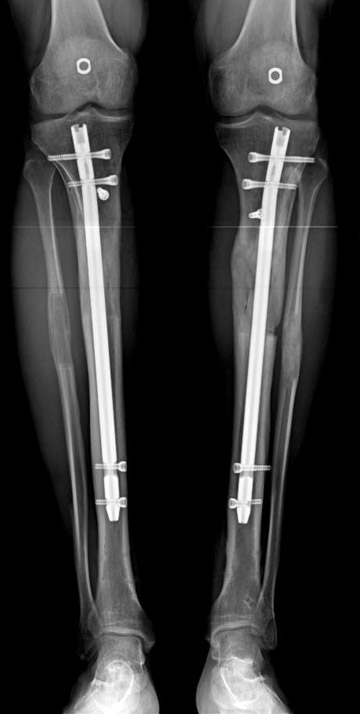

Eksternal fiksatör uygulanımı: İntramedüller çiviye değmeden aşağıya ve yukarıya üçer adet Schanz vidası gönderilir. Vidalarla çivi arasında en az 1 mm den fazla mesafe olmalıdır.

Postoperatif Bakım: Distraksiyona (Kemik parçalarının arasının birbirinden uzaklaştırılması yöntemi) 10. günde başlanır. Günde 4 defa 6 saatte bir 0.25mm uzatma yapılır. Operasyondan 1-2 gün sonra kalça ve diz çevresi hareketlere başlanır. Alt ekstremite kısalıklarının tedavisi uzun yıllar boyunca hem hasta hem de cerrah için zorluklarla dolu olmuştur. İlizarov’un distraksiyon osteogenezisi kavramını tanımlamasından sonra geliştirilen teknikler bu konuda yeni bir çağın öncüleri olmuşlar ve daha önceki yıllarda görülen komplikasyonların oldukça azaldığı uygulamalar olarak anılmışlardır.

Biz son zamanlarda, seçilmiş vakalarda, uzatma sonrası uzunluğu ve “alignment’ı” korumak amacı ile unilateral dinamik aksiyel fiksatör ve kilitli intramedüller çivi kombinasyonunu tercih etmekteyiz. Bu yöntemin ön şartları medullanın en dar çapının 7 mm.’den geniş olması ve uzatma sonrası distalde en az 8 cm. uzunluğunda çivi kalabilmesidir. İntramedüller çivi hem uzatma esnasında femurun üzerine gelen makaslama ve bükülme kuvvetlerini nötralize etmekte hem eksternal fiksasyon süresini kısaltmakta, hem de yeni oluşan kemiği kırıklara karşı korumaktadır. Serimizde bir vakada subtrokanterik femoral osteotomi yapılmıştır. İntramedüller çiviye rağmen varus angulasyonu oluşması yönünde bir dezavantaj tespit etmedik.

Çocuklarda intramedüller çivi üzerinden uzatmanın bir diğer komplikasyonu olarak çivinin giriş yeri nedeni ile büyük trokanter apofizinin zedelenmesi ve sekonder koksa valga deformitesinin gelişmesi gösterilmektedir. Serimizdeki vakaların biri hariç tümü iskelet matüritesine erişmişlerdir. Oniki yaşında olan bir hastamızda son kontrolde koksa valga deformitesi saptanmamıştır. Vaka, halen takip edilmektedir.

İntramedüller çivi ve eksternal dinamik aksiyel fiksatör kombinasyonu teknik olarak standart İlizarov uygulamalarından daha zordur. Ancak şu avantajlar yöntemi cazip hale getirmektedir; eksternal fiksasyon süresinde kısalma, refraktüre karşı korunma, erken rehabilitasyon, azami hareket genişliği kazanma ve günlük yaşam konforu. Bu avantajlar artan maliyet , artan kan kaybı ve potansiyel derin infeksiyon gibi dezavantajların önüne geçmektedir. Sonuç olarak, bulgularımızın eşliğinde, intramedüller çivi üzerinden femoral uzatma tekniğinin güvenilir ve dayanıklı bir metod olduğunu ve bizce standart İlizarov uygulamalarına üstünlük sağlayan avantajlar getirdiğini söyleyebiliriz.